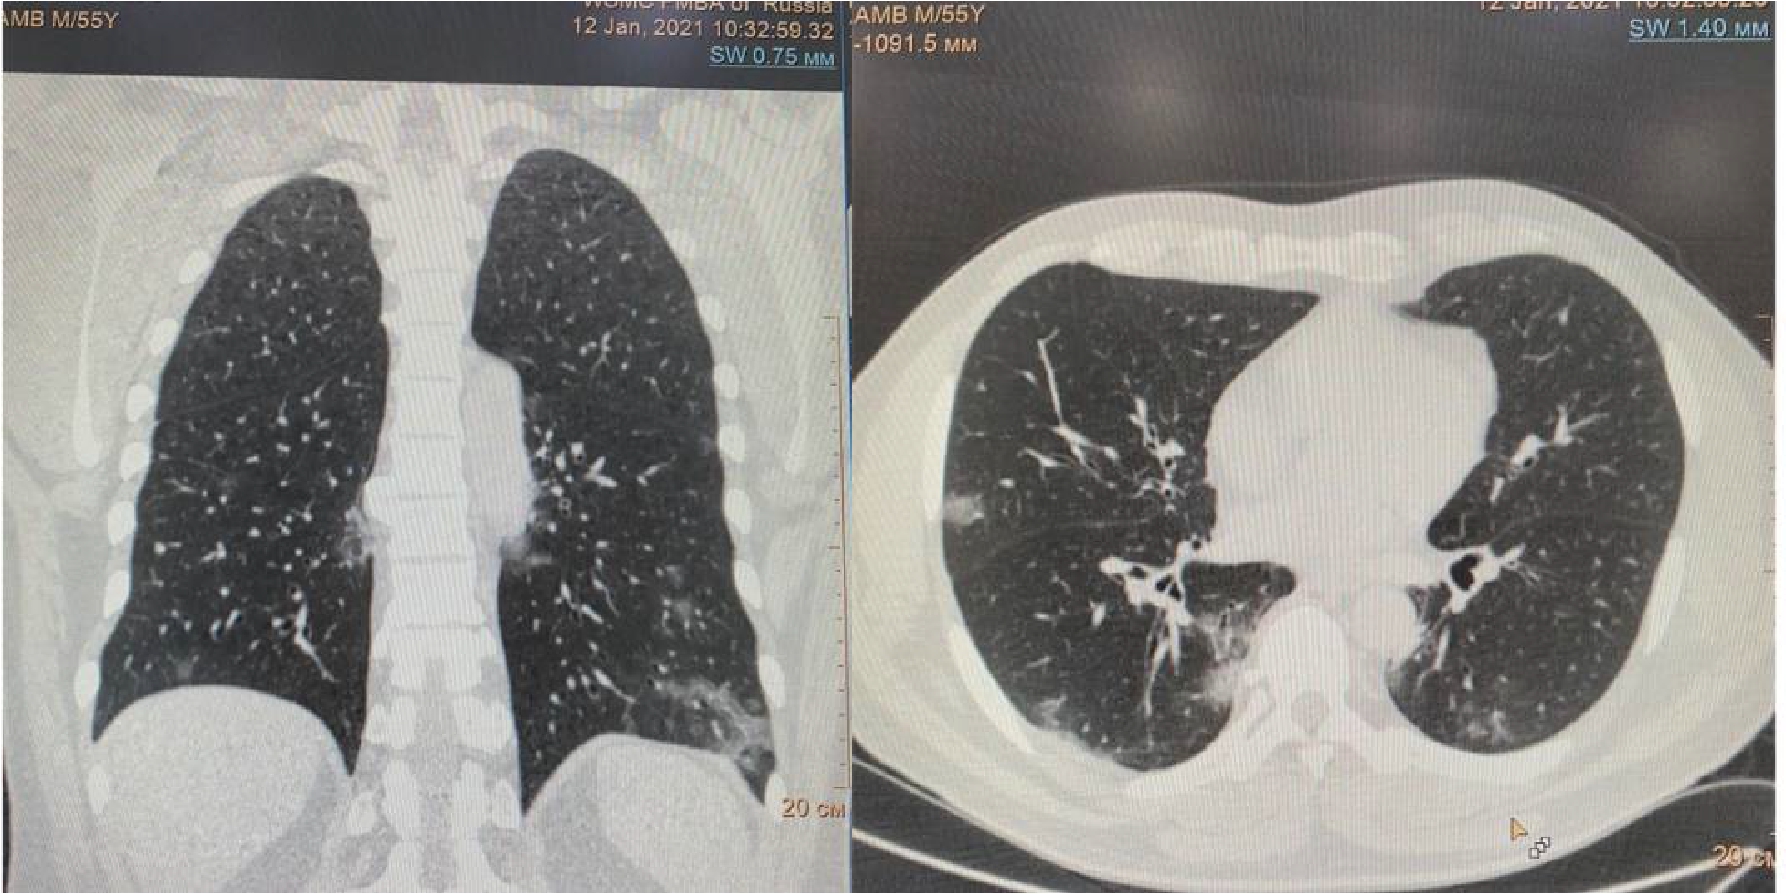

Рисунок 1. МСКТ органов грудной клетки – признаки двусторонней полисегментарной интерстициальной пневмонии (объем поражения 20%, КТ-1).

Пациент (мужчина) 55 лет поступил в стационар с жалобами на сухой кашель, нарушения обоняния и вкуса, одышку при нагрузке, ощущение тяжести в грудной клетке, слабость, боли в мышцах и повышение температуры тела до 380 С. Больной обратился за медицинской помощью на 5 сутки после появления симптомов ОРЗ в связи с неэффективностью самостоятельного лечения и появлением одышки. При поступлении по данным МСКТ легких – признаки двусторонней полисегментарной интерстициальной пневмонии с объемом изменений в пределах 20%, КТ-1 (рис.1). Короновирусная инфекция была подтверждена результатами ПЦР. При поступлении состояние было расценено как средне-тяжелое.